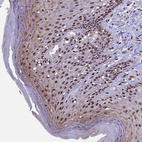

Immunohistochemical staining of human Testis shows strong nuclear and cytoplasmic positivity in cells in seminiferous ducts and Leydig cells.